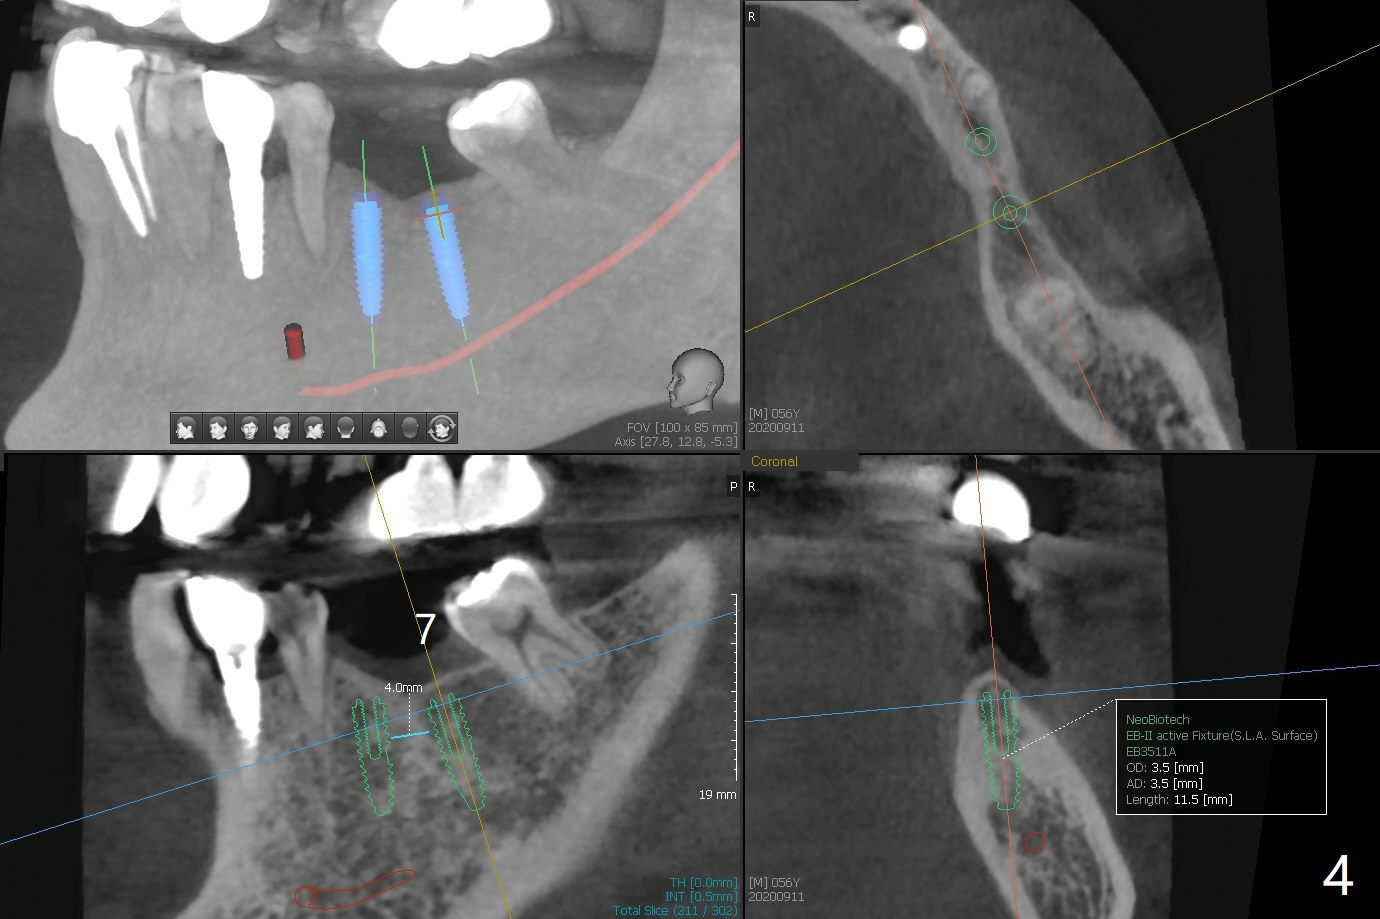

56岁男,高血压,紧张怕痛,要求迅速手术,所以我们初步选择导航。由于他还能在右边咀嚼,先做左侧植牙。左侧好像缺失两个牙齿(图一),不过近远中间隙更象缺失一个牙齿(图二)。牙槽嵴狭窄,骨皮质厚,容易植骨吗?还是容易劈开?牙槽嵴狭窄(图三,四,六)似乎适合种植两个小植体(两个双尖牙)。如果只植入一个,牙槽骨高度差些,植体短(图五),仿佛做牙槽嵴劈开术比较好。